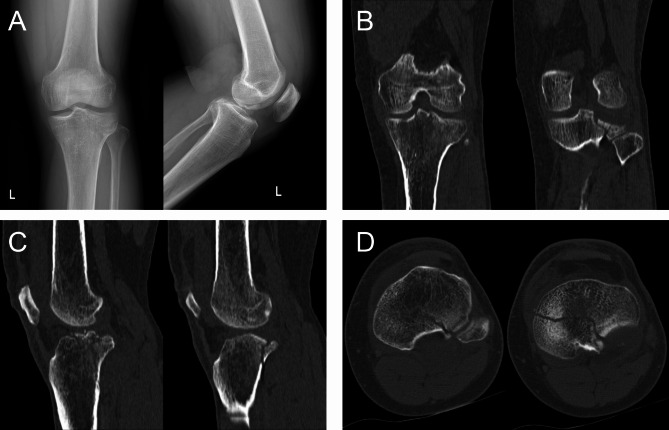

Typical case

Here, we present a case of a 49-year-old male who was admitted to our hospital due to pain, swelling and limited mobility of left knee joint for two hours after a traffic accident. Figure 2 shows the preoperative X-ray and CT scan of the fracture. The features of the injured tibial plateau were clearly displayed (Fig. 3) using the region growing and mask-editing technique of Mimics software version 18.0. Subsequently, an accurate 1:1 model of the injured tibial plateau was 3D printed, allowing the surgeon to observe and manipulate the exact replica of the fractured fragment for actual open reduction. The results of the simulated surgery are shown in Fig. 3. The actual surgery was then guided by the simulated surgery. Postoperative review of X-ray and CT images showed satisfactory fracture reduction and fixation (Fig. 4). The positioning of the plate and screws were good. The patient was followed up for 15 months during which he did not experience any surgical complications and demonstrated excellent Rasmussen’s functional score, as shown in Fig. 5.

Fig. 2.

The patient’s preoperative radiological characteristics of PTPF. A. The anteroposterior and lateral X-ray. B, C, D. The coronal, sagittal and transverse CT images of PTPF